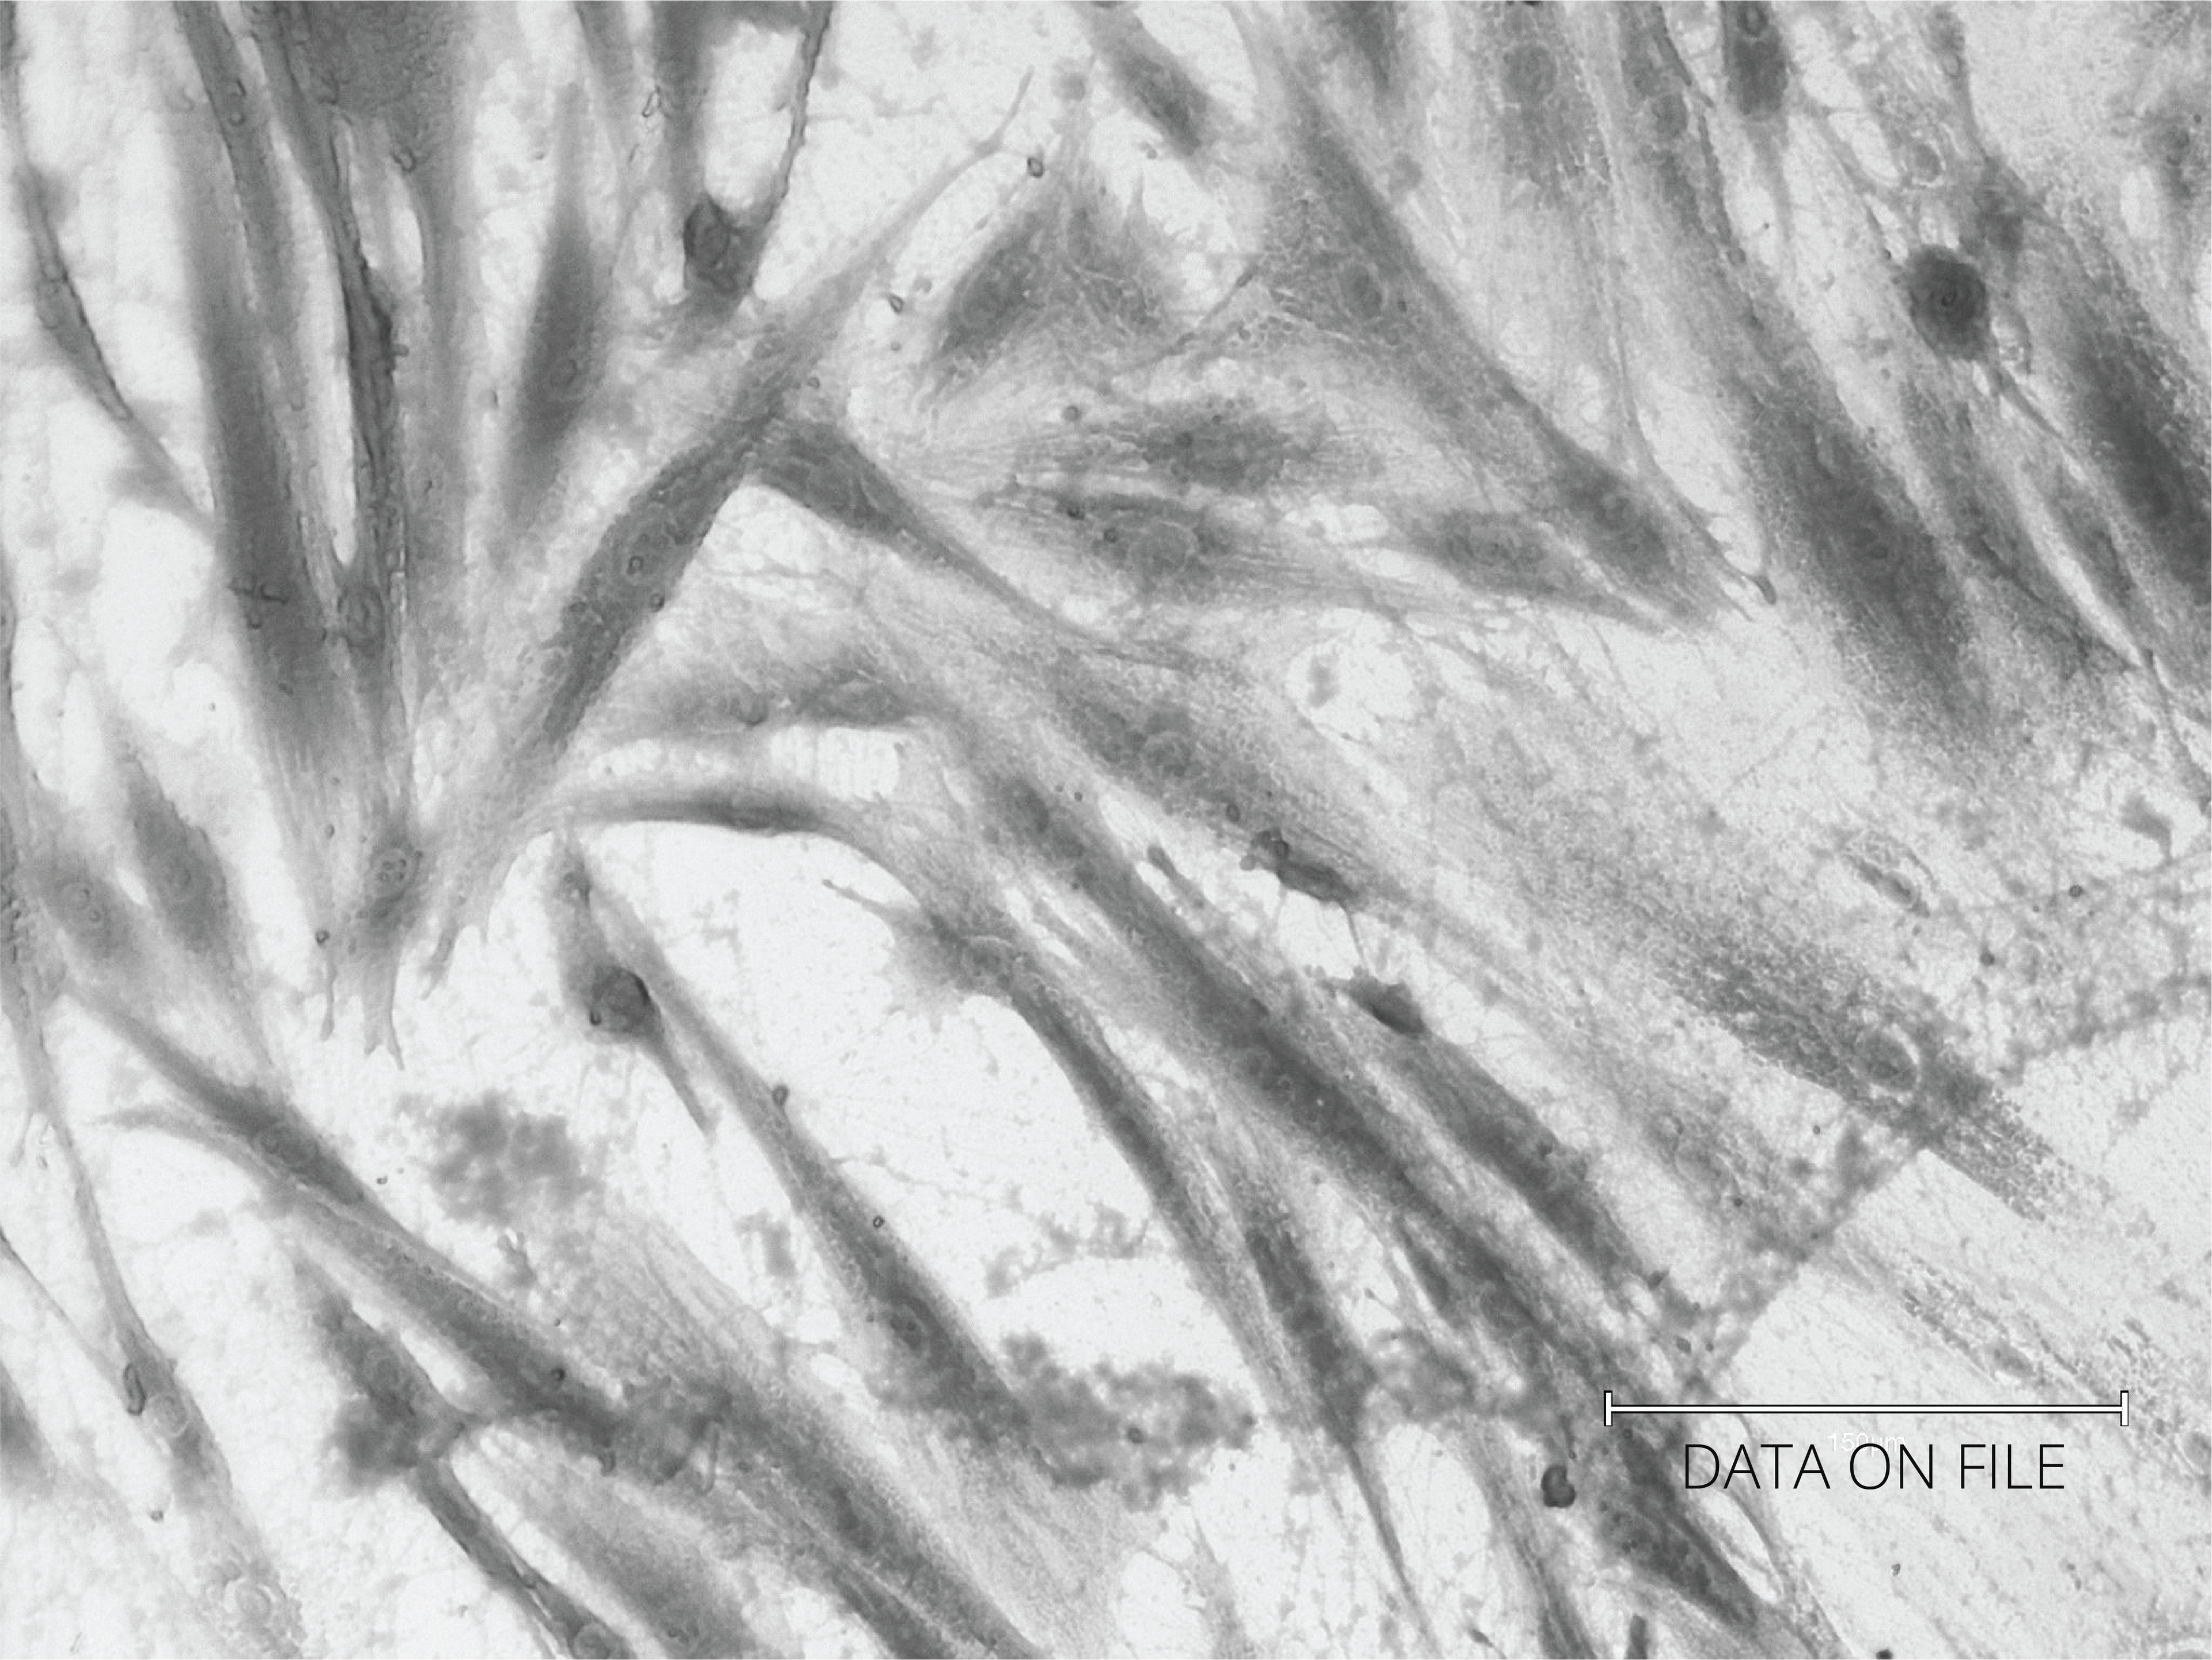

Exhausted Fibroblast Before RLX-201

No Treatment (Control)

Cultured fibroblast from abdominal skin; fibroblast cells with reduced metabolic activity, pre-senescent phenotype, indicating exhaustion and cellular fatigue